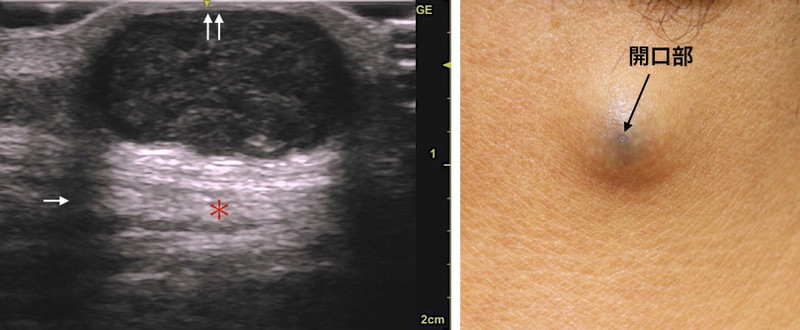

今回の症例も頚部の粉瘤腫で、くりぬき法を行います。

消毒&局所麻酔後に、いつものように4mmトレパンで穴をあけます。

腫瘍の袋も絞り出されました。できるだけまわりの組織に触れないように袋を取り出します。慎重に!